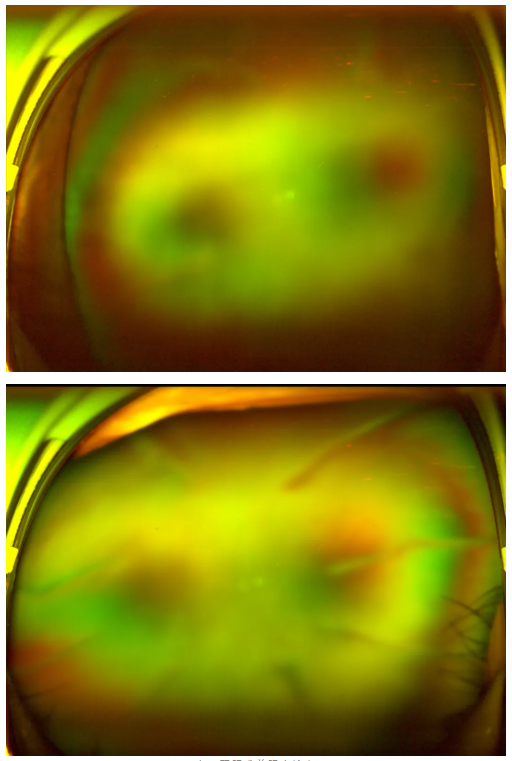

糖尿病視網(wǎng)膜病變

老王雙眼術(shù)前眼底檢查

王曉波主任告知老王:術(shù)后復(fù)查眼底顯示,其糖尿病視網(wǎng)膜病變并不嚴(yán)重,因此視力得以得到明顯改善與提升。當(dāng)初堅持治療、不輕言放棄,是非常正確的選擇!